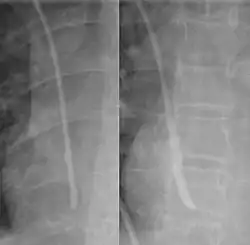

The line is then inserted using the Seldinger technique: a blunt guidewire is passed through the needle, then the needle is removed. A dilating device may be passed over the guidewire to expand the tract. Finally, the central line itself is then passed over the guidewire, which is then removed. All the lumens of the line are aspirated (to ensure that they are all positioned inside the vein) and flushed with either saline or heparin.[1] A chest X-ray may be performed afterwards to confirm that the line is positioned inside the superior vena cava and no pneumothorax was caused inadvertently. On anteroposterior X-rays, a catheter tip between 55 and 29 mm below the level of the carina is regarded as acceptable placement.[37] Electromagnetic tracking can be used to verify tip placement and provide guidance during insertion, obviating the need for the X-ray afterwards.

Chest x-ray with catheter in the right subclavian vein -

The outline of superior vena cava on a chest X-ray is labeled at left.